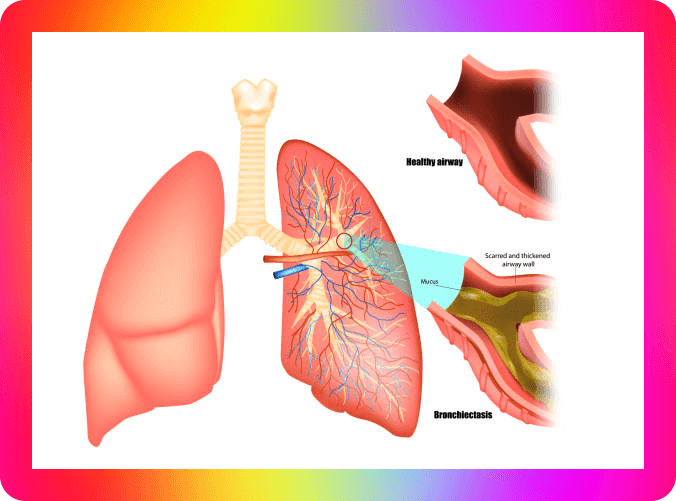

- 화농성 가래 - 폐렴, 폐농양, 기관지 확장증

화농성 가래는 고름과 같은 형태이고 점액성 가래는 끈적거리는 특징으로 알려져 있으며 관련 합병증 종류는 아래와 같은 질환이 있다고 합니다.

- 기관지 확장증